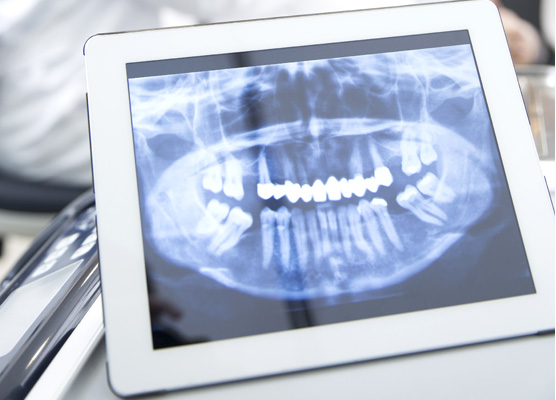

CBCT